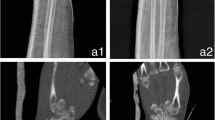

All 3D printing processes require significant manual postprocessing effort. Specialized postprocessing stations and dedicated space is needed. These tasks include support structure removal and cleaning. Close collaboration between physicians and technical staff appears to be the most efficient manpower arrangement. On-site dedicated staff proficient in image segmentation, anatomical knowledge and operation of 3D printers are necessary. Having orthopaedic surgeons trained in 3D printing skills can improve the utilization rate of the printing facility; however, unforeseen, emergency 3D printing orders may impede efficient running (Fig. 4).

Tibial plateau fracture model in acrylonitrile butadiene styrene copolymer (ABS; Fortus450mc/ABS-M30i, Stratasys, Eden Prairie, MN, USA). a, b Removal of intramedullary support structures and in the cancellous fracture gaps can be very time consuming. c, d Powder fusion with selective laser sintering (SLS; P110/PA2200, EOS, Krailling, Germany) demonstrating production of multiple objects in a single machine cycle before (c)and after (d) powder removal